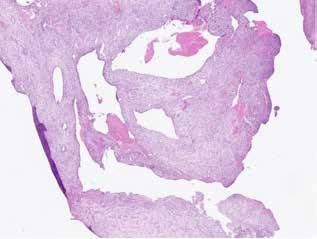

deltaa@ddeltaa--rengoering d dk

www.delta-rengoering.dk

Hvis jobannoncen bliver indrykket på både Dentaljob.dk og i Tandlægebladet, får du 50 % rabat på annoncen i bladet

BAGGRUND – Centralt kæmpecellegranulom (Central giant cell granuloma – CGCG) er en sjælden, godartet læsion, som nærmest udelukkende er lokaliseret til kæberne. Det har kliniske, radiologiske eller histologiske ligheder med flere andre intraossøse læsioner. Ætiologien er stadig ukendt, men det viser sig, at genetiske mutationer er associeret med forekomsten af CGCG.

PATIENTTILFÆLDE – Tre drenge i alderen fem og seks år blev alle diagnosticeret med og behandlet for større CGCG-læsioner med få måneders mellemrum på Tand-, Mund- og Kæbekirurgisk Klinik, Aarhus Universitetshospital.

KONKLUSION – Det er yderst relevant at følge børn med spontant og tidligt tandtab i kommunal tandpleje. Ved mistanke om patologiske forandringer henvises til hurtig udredning og diagnostik i hospitalsregi for at klarlægge diagnose og minimere skader på blivende tandanlæg og omkringliggende strukturer.

EMNEORD Central giant cell granuloma | giant cell lesions | jaw neoplasm | benign bone diseases

CHRISTIAN LIND AXELGAARD, specialtandlæge i tand-, mund- og kæbekirurgi, Speciialklinik for kæbekirurgi, Silkeborg

KIMIE BOLS ØSTERGAARD, tandlæge i videreuddannelse til specialtandlæge i tand-, mund- og kæbekirurgi. Kæbekirurgisk Afdeling, Aalborg Universitetshospital

SVEN ERIK NØRHOLT, klinisk professor, specialtandlæge i tand-, mund- og kæbekirurgi, ph.d., overtandlæge, Afdeling for Tand-, Mund- og Kæbekirurgi, Aarhus Universitetshospital, og Sektion for Kæbekirurgi og Oral Medicin, Institut for Odontologi og Oral Sundhed, Aarhus Universitet

PER JOHAN SIXTEN BLOMLÖF, overtandlæge, docent, ph.d., specialtandlæge i tand-, mund- og kæbekirurgi, Afdeling for Tand-, Mund- og Kæbekirurgi, Aarhus Universitetshospital

STEEN BÆRENTZEN, overlæge, Patologiafdelingen, Aarhus Universitetshospital